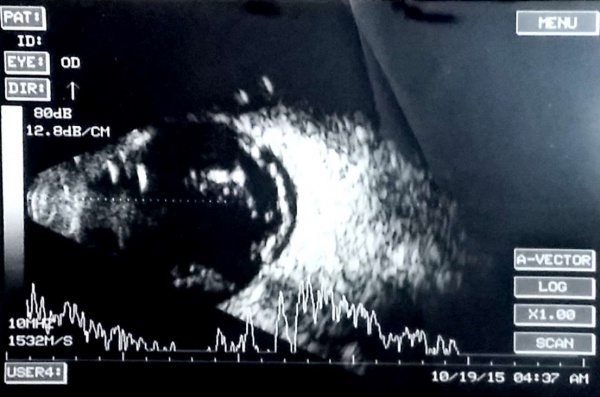

Note the after-movements of the PVD in this patient with subhyaloid hemorrhage and vitreous hemorrhage.